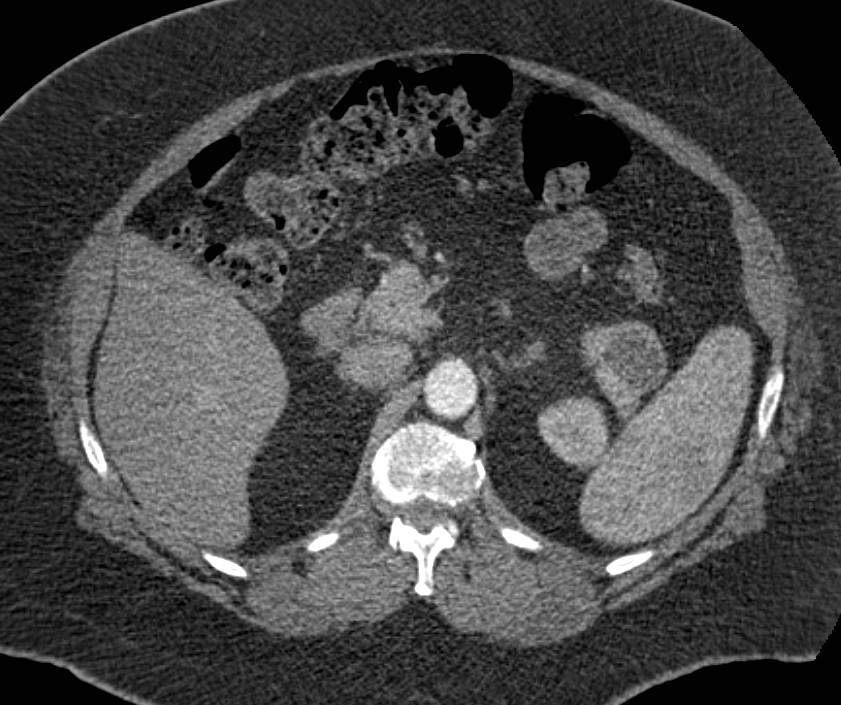

Pancreatic Cancer Invades and Obstructs the Duodenum